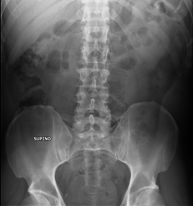

- RX Abdomen

Tècnica que usa els raigs X a través de la qual s'obtenen imatges de l'abdomen (estómac, intestí prim, intestí gros, fetge, ronyons, bufeta, pelvis òssia, etc.) per al seu estudi. - RX Columna lumbar